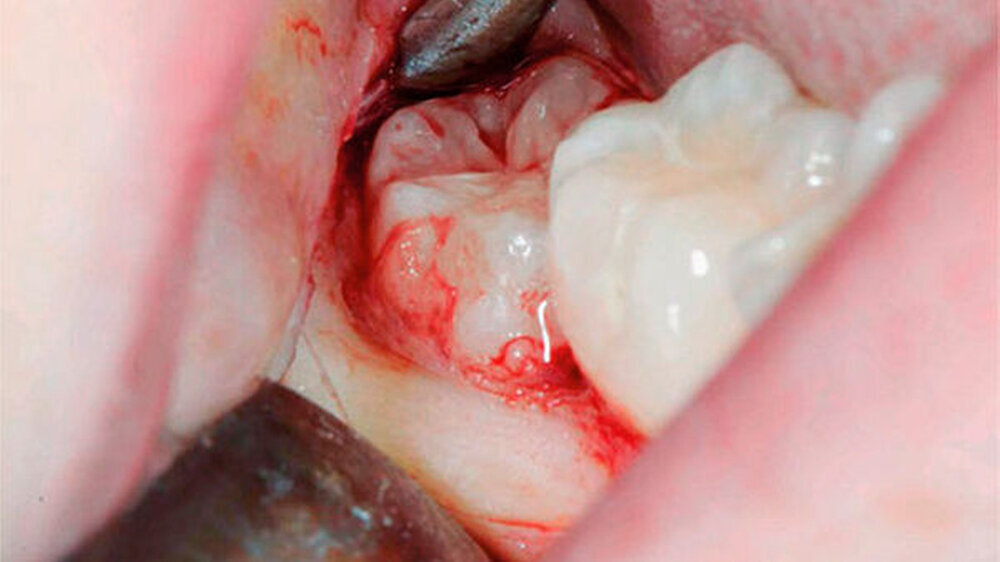

Die Koronektomie wurde, wie in Abbildungen 1a bis k gezeigt, durchgeführt. Die Schnittführung erfolgte intrasulkulär beim Nachbarzahn mit kurzer disto-bukkaler Entlastung über dem Ramus ascendens. Anschließend wurde ein bukkaler Mukoperiostlappen gebildet. Die Zahnkrone, welche von Knochen bedeckt war, wurde mit dem Handstück und dem Rosenbohrer unter ständiger NaCl-Kühlung bis zur Schmelz-Zement-Grenze freigelegt.

Anschließend wurde mit einem Fissurenbohrer die Krone an der Schmelz-Zement-Grenze abgetrennt. Es wird empfohlen, den Fissurenbohrer nur so weit in den Zahn vordringen zu lassen, dass die lingualen Weichgewebe nicht verletzt werden.

Danach wurde die Krone mit dem Hebel abgetrennt. Dabei ist darauf zu achten, dass die Wurzel nicht anluxiert wird. Falls der Wurzelblock nach dem Dekapitieren eine verstärkte Mobilität aufweisen sollte, muss aufgrund einer erhöhten Infektionsgefahr eine komplette Extraktion durchgeführt werden.